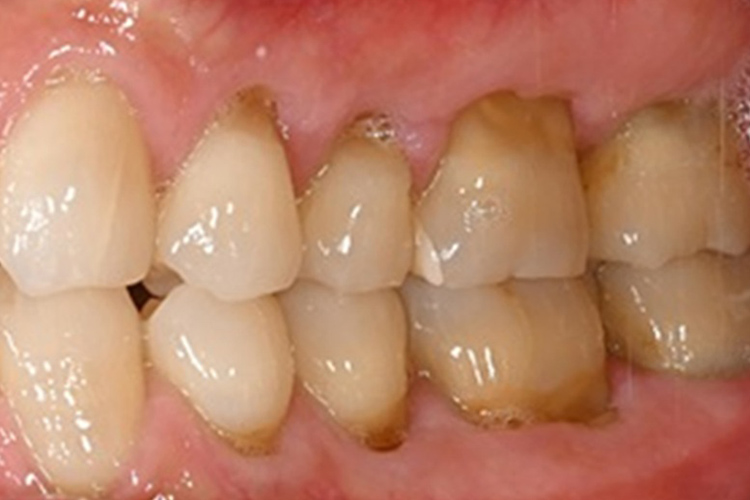

この患者様は、口腔内全体において重度の歯周病が生じており、歯磨き指導、クリーニング、Flap手術等を行ったが、歯周ポケットが深すぎるためブルーラジカル適用症例と診断し、施術を行いました。

施術前のレントゲンと口腔内写真です。施術前にプラークの除去を行ってから、施術します。

この患者様は、スケーリングより歯周ポケットが6mm以上ある患者様で患者様ご本人も歯周病になりかけている自覚がありました。

また、口臭も気になされていましたので、ブルーラジカルの適用症例と判断し、施術を行いました。

施術前のレントゲンと口腔内写真です。